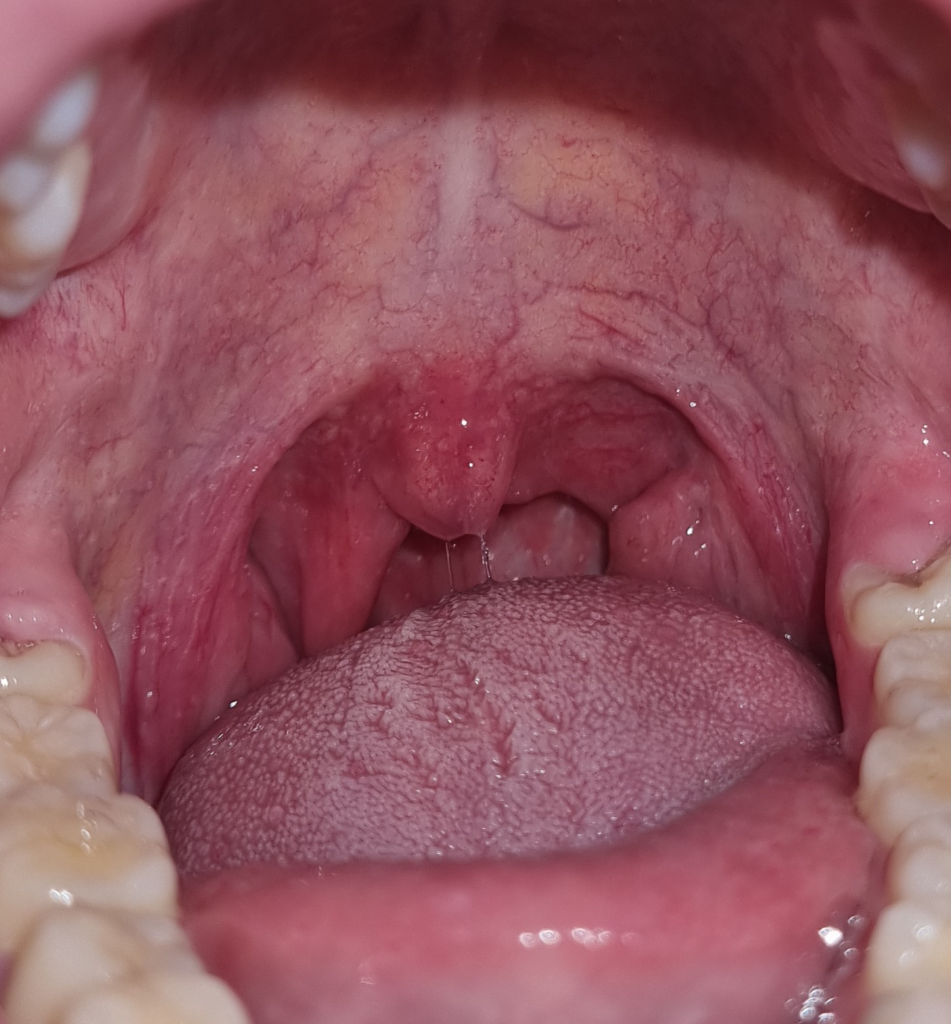

인두와 편도가 많이 부은것 같습니다.

많이 붉어져있고 편도도 부어있습니다.

가까운 병원에서 대면진료 받으시고 약제 처방받으세요.

타이레놀이나 소염진통제를 추가로 복용하시고 소염제 성분의 스프레이를 목에 뿌리시는게 도움이 되겠습니다.